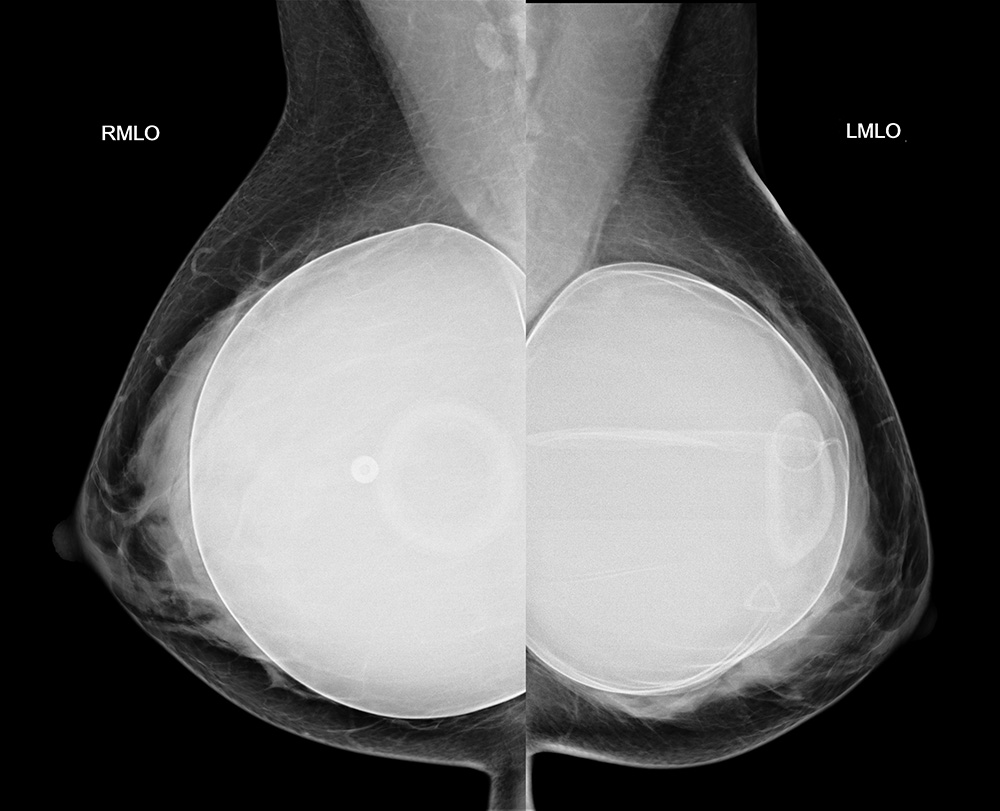

◂Breast Anatomy